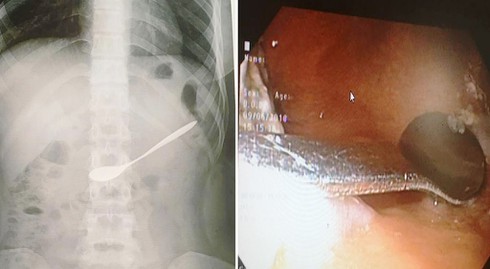

Hình ảnh chiếc thìa nằm trong ổ bụng của bệnh nhân. |

Ngay khi tiếp nhận nữ bệnh nhân, qua kiểm tra và thăm khám, các bác sĩ phát hiện chiếc thìa nằm tại hang vị dạ dày. Sau đó đã tiến hành gắp dị vật này ra khỏi người bệnh nhân.